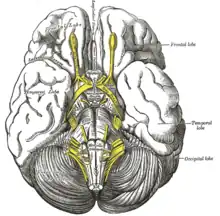

Mésencéphale et rhombencéphale (vue postero-latérale).

Base du cerveau.